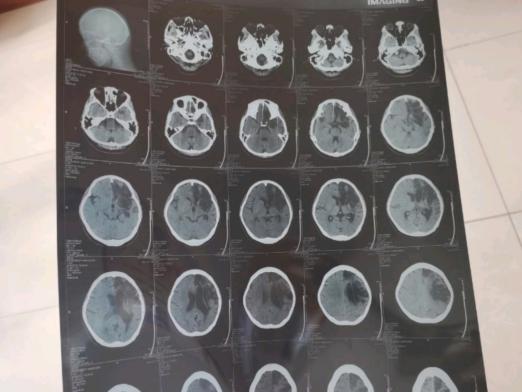

辅助检查:自备头部影像报告示脑梗死。

西医诊断:脑梗死